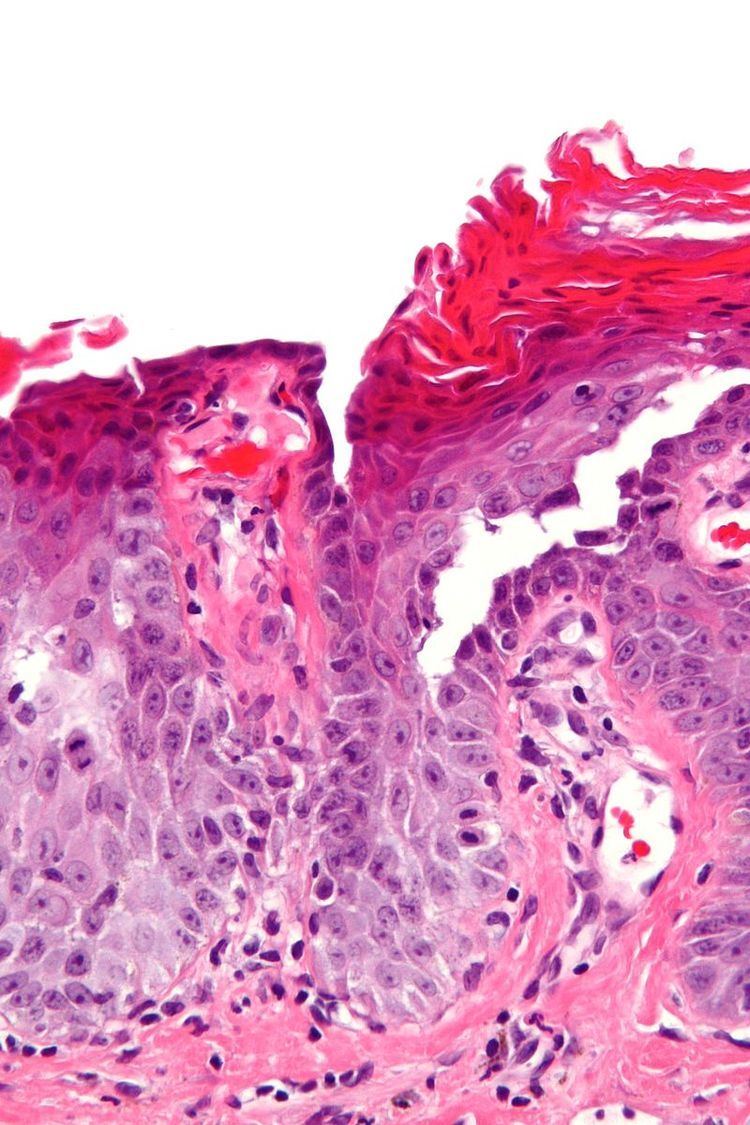

Grover's disease (GD) is a polymorphic, pruritic, papulovesicular dermatosis characterized histologically by acantholysis with or without dyskeratosis. Once confirmed, most cases of Grover's disease last six to twelve months, which is why it was originally called "transient". However it may last much longer. Nevertheless, it is not to be confused with relapsing linear acantholytic dermatosis.

Grover's may be suspected by its appearance, but since it has such a characteristic appearance under the microscope a shave skin or punch biopsy is often performed.